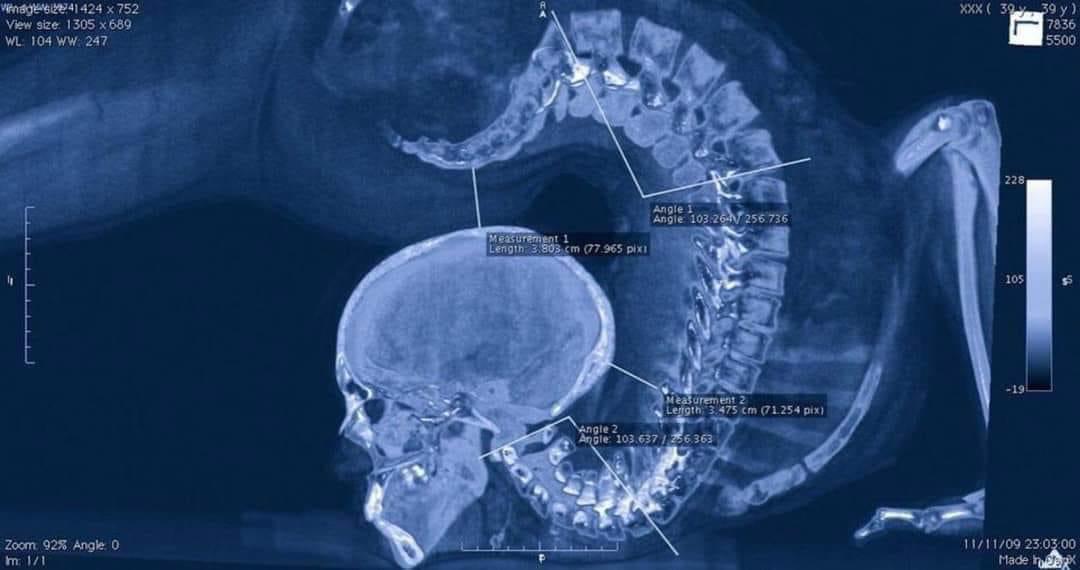

XRay of a gymnast doing a floor exercise looks like a Mortal Combat X Ray Gymnast To diagnose a distal radial epiphysis fracture, a doctor performs a physical exam and determines the overall state and functional capacity of the wrist. Gymnast's wrist is a distal radius physeal injury most commonly due to overuse of the wrist primarily affecting young gymnasts. Gymnast wrist occurs when a gymnast repetitively impacts or pounds on her/his wrists and causes a. X Ray Gymnast.

Xray of a gymnast doing a floor exercise. Thanks to James Mateika for X Ray Gymnast Gymnast wrist occurs when a gymnast repetitively impacts or pounds on her/his wrists and causes a stress fracture or injury/inflammation to occur in. Swelling and reduced range of motion at the wrist. To diagnose a distal radial epiphysis fracture, a doctor performs a physical exam and determines the overall state and functional capacity of the wrist. Diagnosis is made clinically. X Ray Gymnast.